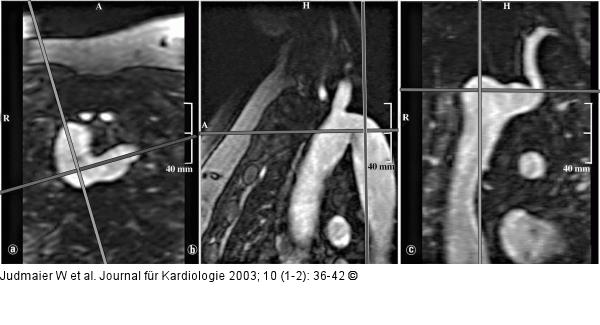

Abbildung 6a-c: Magnetresonanzangiographie - multiplanare Rekonstruktion MPR - multiplanare Rekonstruktion; diese Technik erlaubt, den 3-D-Datensatz in beliebiger Orientierung zu schneiden und damit achsenparallele Gefäßlängs- und -querschnitte zu generieren. |

Abbildung 6a-c: Magnetresonanzangiographie - multiplanare Rekonstruktion

MPR - multiplanare Rekonstruktion; diese Technik erlaubt, den 3-D-Datensatz in beliebiger Orientierung zu schneiden und damit achsenparallele Gefäßlängs- und -querschnitte zu generieren. |